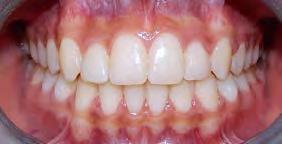

El tiempo de tratamiento fue de 2 años y 9 meses se lograron los objetivos del tratamiento manteniendo el perfil facial, y las relaciones esqueléticas maxilomandibulares. Se realizó la tracción del 13, la corrección de rotaciones dentales en el maxilar, se mantuvo la clase I molar izquierda y se obtuvo la clase I molar derecha. La clase I canina izquierda, y se logró la clase I canina derecha, cerrar mordida abierta de sectores laterales, corrección del overjet y overbite, corrección de líneas medias dentales, manejo de Bolton de arcada superior, mejorar estado periodontal, lograr correcta intercuspidación, guía de desoclusión canina y guía incisiva y la restauración de los dientes 12 y 22

(Figura 5). Una vez terminado el tratamiento, la estabilidad a largo plazo mediante la retención con un circunferencial con finger en los incisivos 12 y 22 para la arcada superior y retenedor termoformado para la arcada inferior.

Radiografía panorámica final el canino 13 es incorporado al arco (Figura 5) y los terceros molares en etapa de formación.

Estudios intraorales finales en las fotografías oclusales, se ven los laterales 12 y 22, así como la incorporación del canino al arco con torque adecuado (Figura 6). En la lateral derecha e izquierda la restauración estética de los laterales superiores,

sin rotaciones ni discrepancia de Bolton.

Figura 5. Radiografía Panorámica. Figura 6. Comparación inicio-final en oclusión.